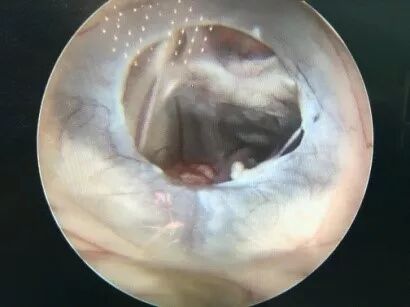

二次内镜探查可见造瘘口及导水管都是通畅的,考虑患儿存在交通性脑积水,医生使用贝朗蛇牌proGAV2.0分流管 进一步为患儿做了脑室腹腔分流术。